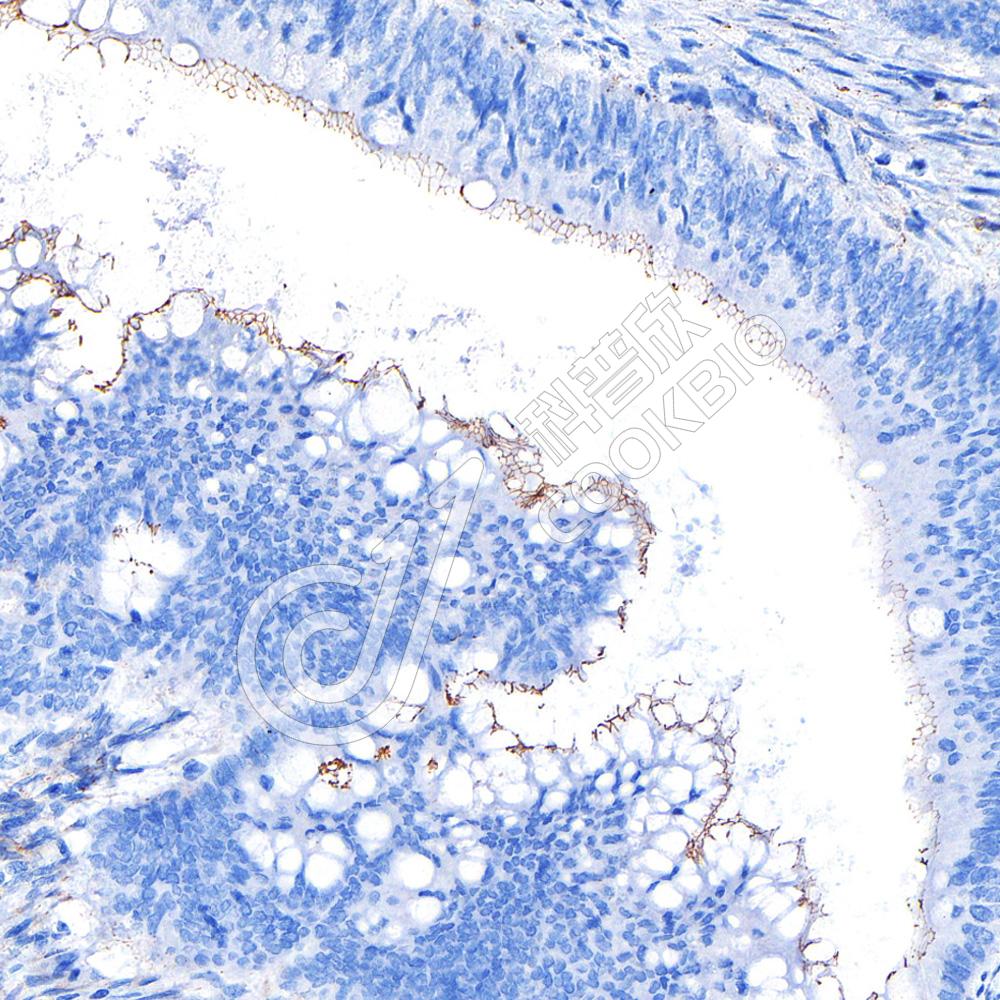

IHC检测PRPH2/RDS蛋白(货号 K1340761).

样品: 小鼠眼球, 4%多聚甲醛 (货号KSG1101) 固定12-24小时.

抗原修复: 柠檬酸抗原修复液(干粉, pH 6.0) (KSG1201), 98℃, 20分钟.

—抗: 1: 3000稀释, 4℃ 孵育过夜.

二抗: S-vision免疫组化多聚二抗(山羊抗兔),即用型 (货号KB3906), 室温孵育20分钟.